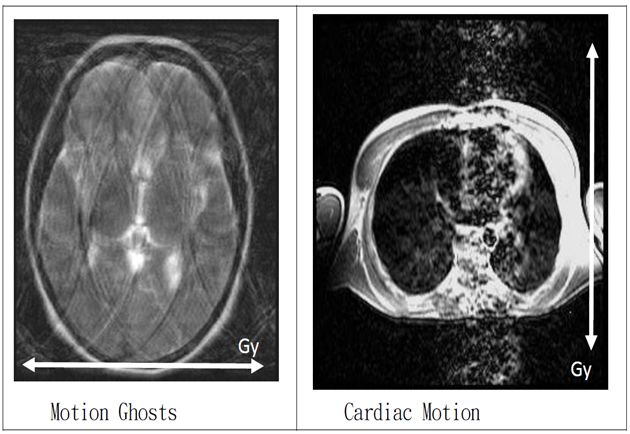

運動假影(Motion artifacts):

大致可分成:隨機性移動(Random motion)、周期性移動(Periodicnmotion)

隨機性移動:病患有意識或者無意識的移動,例如:咳嗽、吞嚥、顫抖…等

周期性移動:像是心臟、CSF、血液的流動…等n

主要發生在相位編碼(phase encoding)方向。

因為

1.沿著任何磁場梯度的移動會造成不正常的相位累積,並沿著相位編碼梯度的方向錯置。

2.在相位編碼方向得到訊號所需要的時間,遠較在頻率編碼方向長,使移動假影多沿著相位編碼方向延伸